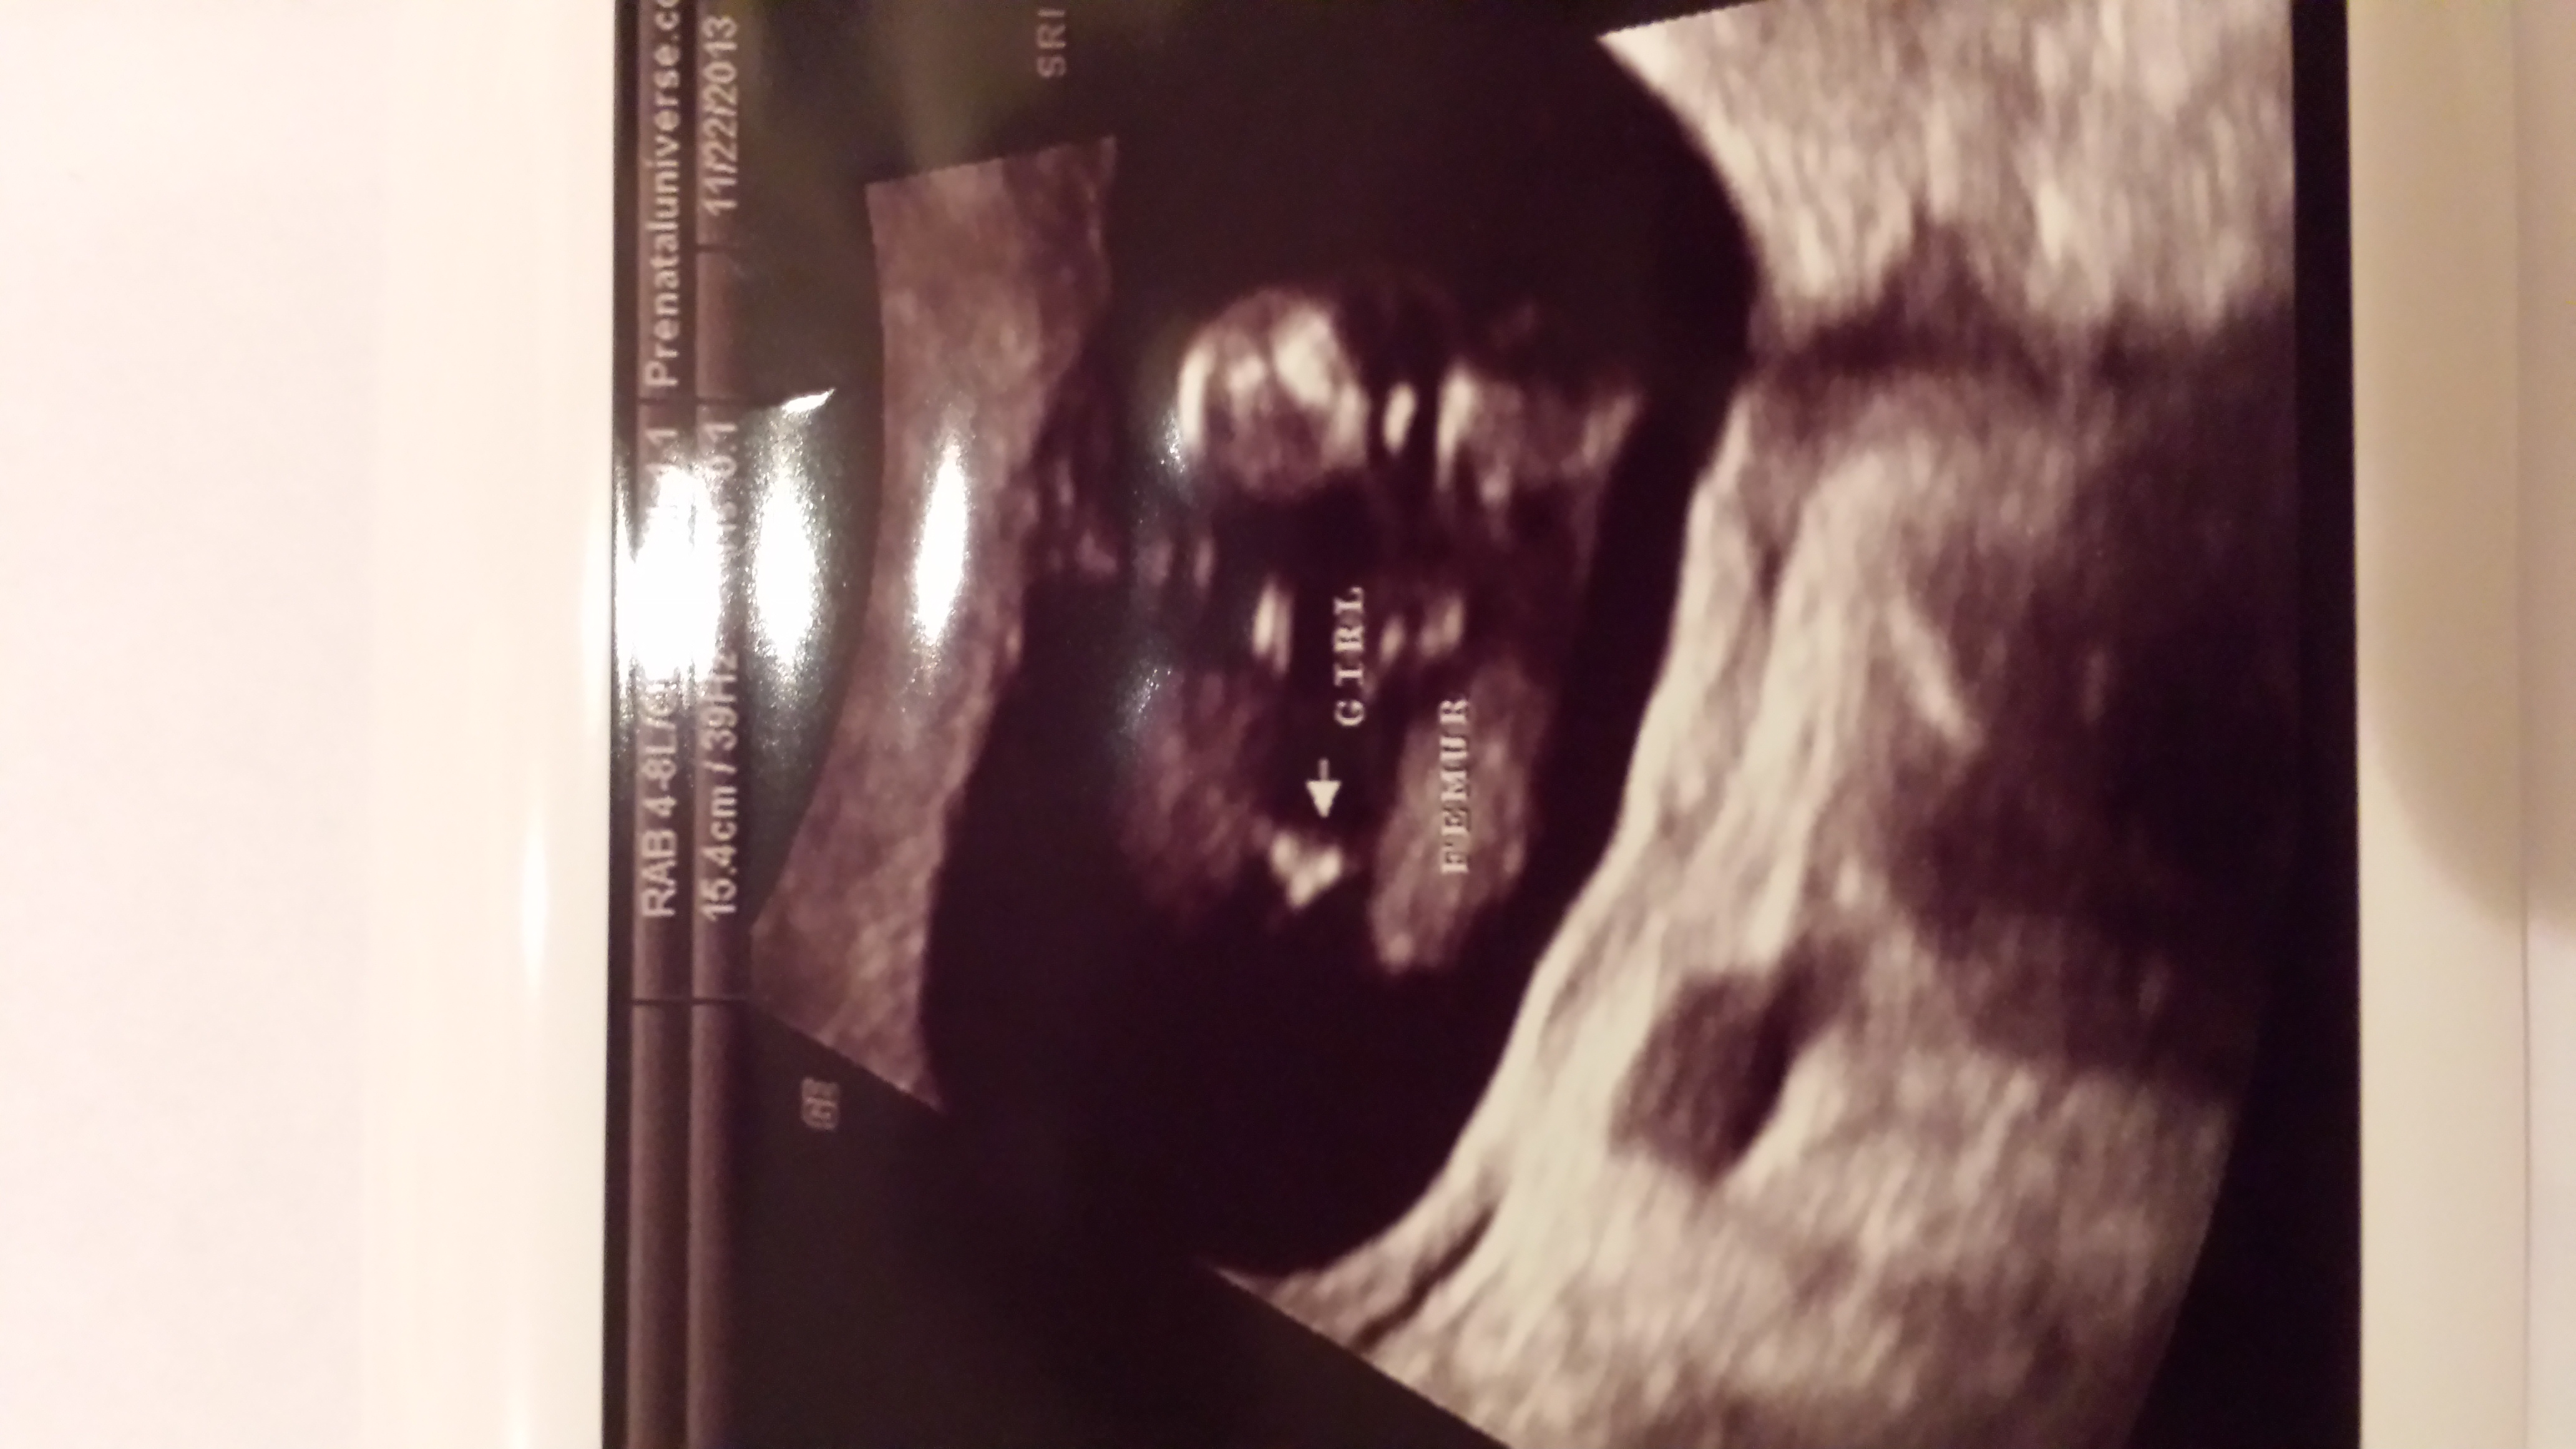

Had a 16w6d ultrasound yesterday...tech sounded 100% sure this was a girl. He said he didn't see any boy parts, and then when he snapped this pic, he said, "Yep, that's what I was looking for." My husband definitely thinks girl too. I have two boys, and their pics didn't look like this, but I'm just not convinced it's girl!

Looks girl to me too.